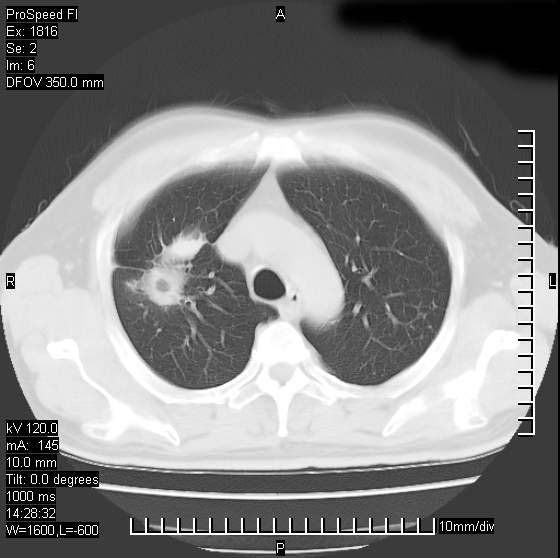

男性,50 ,肺结核9年,咳嗽,胸痛一周。右上肺见一厚壁空洞,周边有点样钙化,胸膜牵拉,洞壁较光整。诊断结核性空洞。有癌性的可能吗? 余肺野无异常,没有上传。

洞壁比较光整,考虑结核性空洞,最好再取原片比较下

洞壁较厚内壁比较光整,考虑结核性空洞,最好再取原片比较下或薄扫一下

不像是肺ca倒更像一个结核空洞,因为看一下他内前方的支气管一点没有浸润征象只是压迫.

洞壁较厚内壁比较光整,两个病灶有关联性,纵隔淋巴结不大,考虑结核性空洞。

结核有可能,肺癌待排。空洞的前上还方见一软组织结节影。

部分层面见空洞为近似新月形,洞壁内缘尚规整且近肺门侧,周围见索条影、卫星灶,结合病史,首先考虑肺tb可能大。

9年的结核应该呈现多形态病灶,该病例只能见到少许纤维索条影,似乎与结核的演变不太相符。空洞内壁不光整,外侧伴有胸膜粘连,考虑癌性空洞可能性大,期待结果。

内壁光滑,周围有卫星灶,还是结核可能性大,但壁太厚,应密切观察随访复查